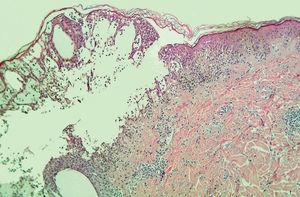

Un estudio analítico sistemático que incluía anticuerpos antinucleares (ANA) y anticuerpos contra la transglutaminasa tisular resultó normal o negativo. Se realizaron dos biopsias. En una de ellas se podía apreciar una ampolla intraepidérmica por espongiosis masiva (fig. 3) y la presencia, en su techo, de microabscesos de neutrófilos. En la otra, el hallazgo más destacable era la presencia de vesículas espongióticas por intensa exocitosis epidérmica de neutrófilos (fig. 4), con focos de daño vacuolar y necrosis de queratinocitos aislados.

Fig. 3.--Vesícula intraepidérmica por espongiosis masiva. (Hematoxilina-eosina, x20.)